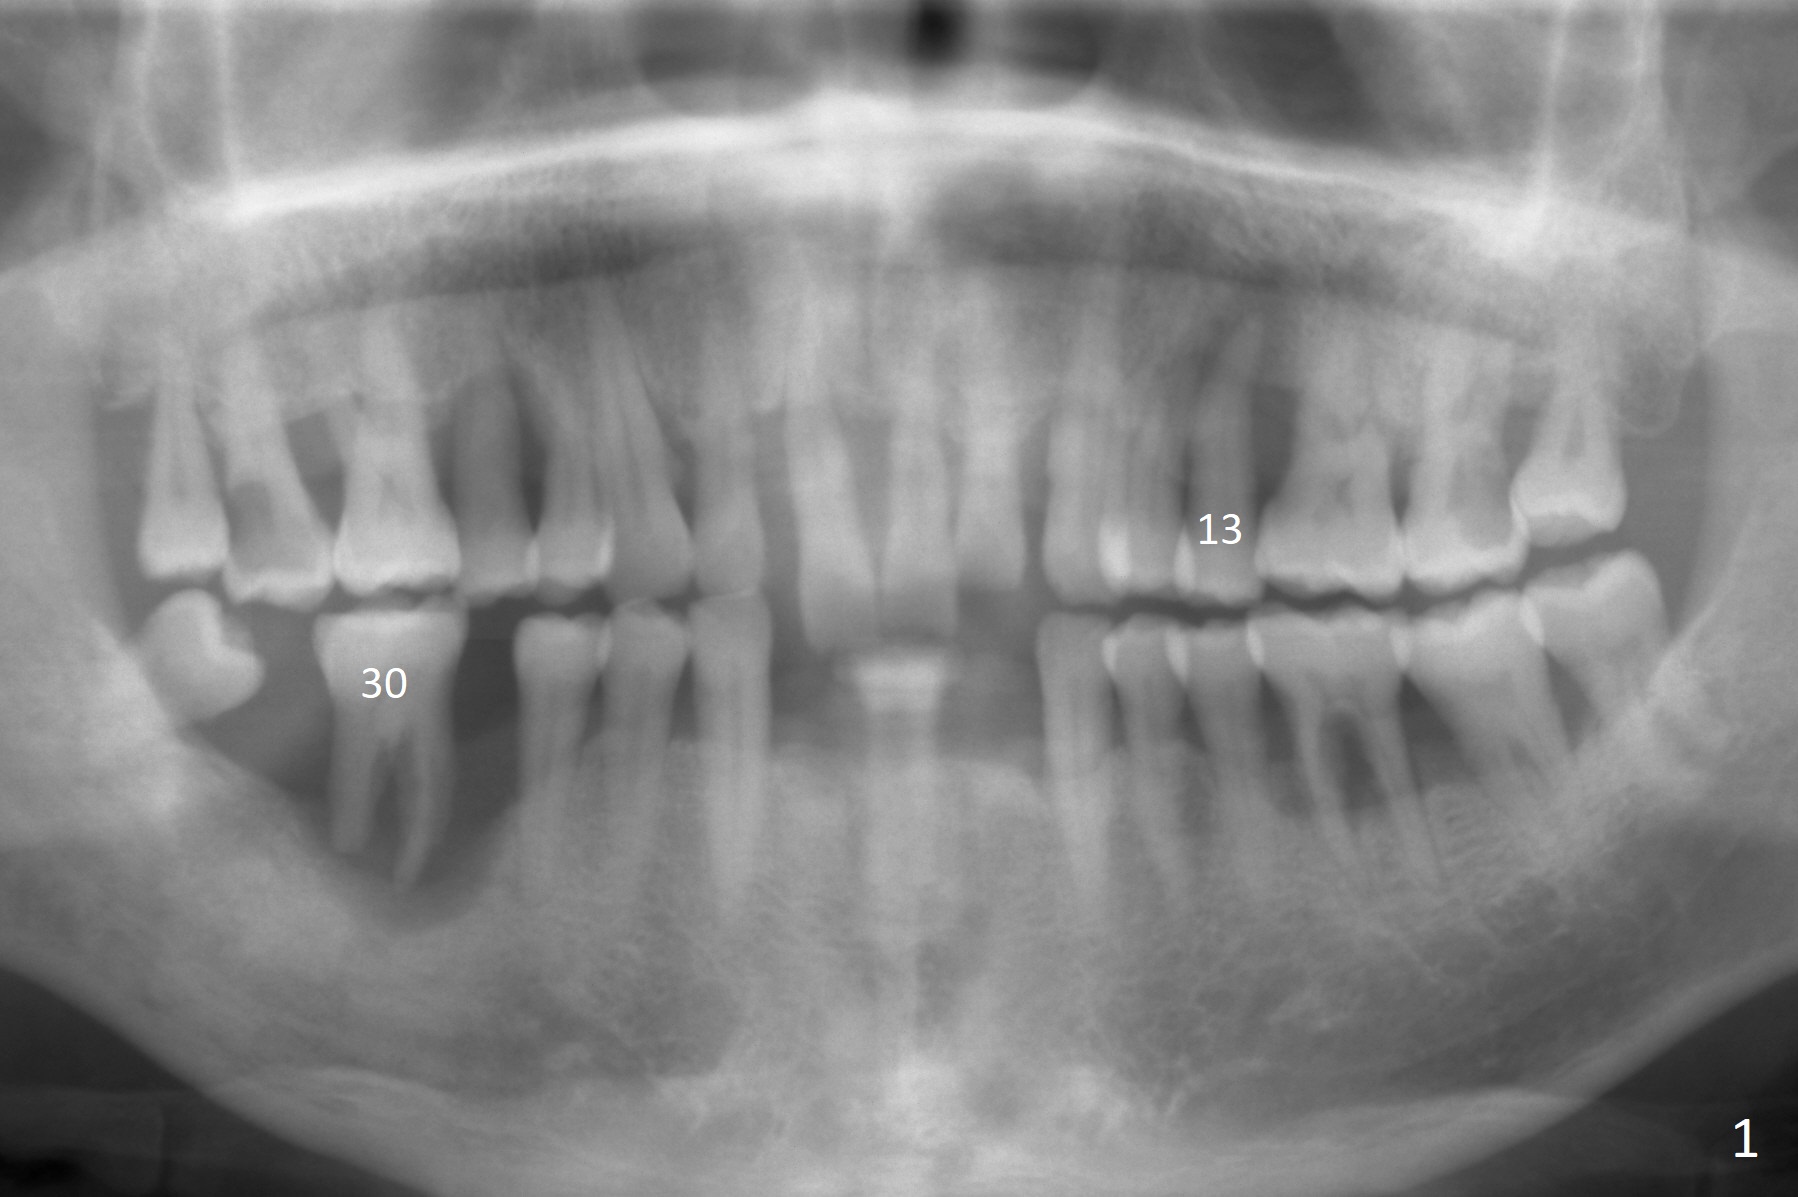

A 57-year-old man has advanced periodontitis with bruxism. The mobile teeth #13 and 30 are his main concern (Fig.1). The tooth #30 has shifted distally. An implant will be placed in the mesial socket, if present. Due to severe bone loss, a 7 mm long abutment with 6 mm cuff is most likely to be used (Fig.2). Since the socket is huge, prepare large piece of gauze for hemostasis. Osteotomy should be initiated as buccal as possible, as the Inferior Alveolar Canal is near the lingual plate at the 1st molar. Prepare Sinus Master Kit. Why? Always take PA after initial drill to avoid violating the Canal. It may be ok to see the overlapping between the parallel pin and the Canal. Do not administer the Inferior Alveolar nerve block.